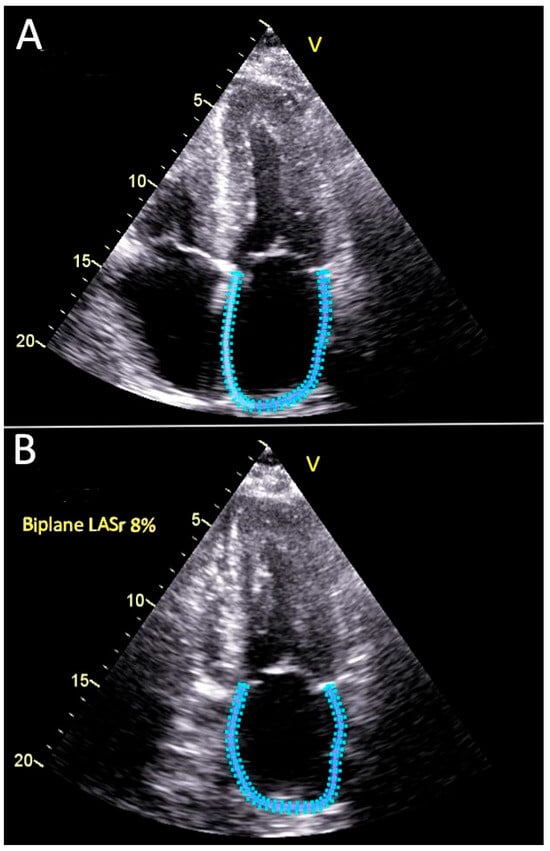

Validation of Manual Method for the Left Atrial Strain Calculation